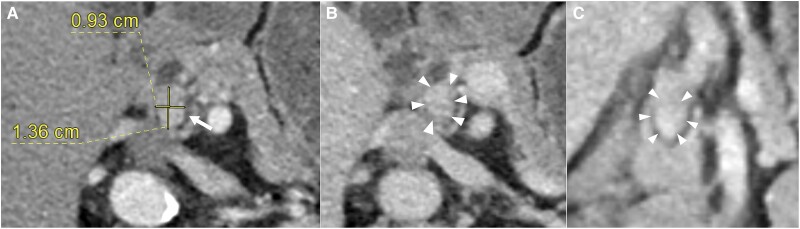

A 75-year-old female presented with fasting hypoglycemic episodes. A supervised fast ended at 72 hours fulfilling Whipple triad, with suppressed insulin and C-peptide levels, but discordantly suppressed serum β-hydroxybutyrate levels. After 21 months of recurring symptoms, a repeat fast ended at 48 hours with Whipple triad, suppressed serum β-hydroxybutyrate level, and borderline nonsuppressed C-peptide level, suggesting endogenous hyperinsulinism. Serum insulin levels were discordantly suppressed. Computed tomography (CT) of the abdomen demonstrated an enhancing 1.36 × 0.93-cm nodule in the head of the pancreas. Endoscopic ultrasound (EUS)-guided fine-needle aspirate of the lesion derived cytology consistent with a neuroendocrine tumor, but fine-needle core biopsy returned normal pancreatic tissue. Because the results were equivocal, functional imaging with 68Gallium-DOTA-exendin-4 positron emission tomography CT was performed, which confirmed the diagnosis of a single head-of-pancreas insulinoma. The patient declined surgical resection. Oral diazoxide therapy resulted in significant peripheral edema. Hence, EUS-guided radiofrequency ablation of the lesion was performed, and the patient remains symptom free 10 months postprocedure. This case illustrates that (1) exendin-4-based positron emission tomography may help one confidently diagnose and localize insulinoma when prior biochemical or endoscopic biopsy results are ambiguous; and (2) EUS-guided radiofrequency ablation is an efficacious alternative option to surgical resection in the frail, elderly patient with insulinoma.

一名75岁女性表现为空腹低血糖发作。监督禁食在72小时结束,满足惠普尔三联征,胰岛素和c肽水平受到抑制,但血清β-羟基丁酸水平受到不一致的抑制。症状复发21个月后,重复快速结束48小时,Whipple三联征,血清β-羟基丁酸水平抑制,边缘非抑制c肽水平,提示内源性高胰岛素血症。血清胰岛素水平被不一致地抑制。腹部计算机断层扫描(CT)显示胰腺头部一个1.36 × 0.93 cm的增强结节。超声内镜(EUS)引导下细针抽吸病变的细胞学表现与神经内分泌肿瘤一致,但细针核心活检显示胰腺组织正常。由于结果不明确,行68镓- dota -exendin-4正电子发射断层扫描CT功能显像,确诊为单发胰头胰岛素瘤。病人拒绝手术切除。口服二氮唑治疗导致明显的外周水肿。因此,eus引导下对病变进行射频消融,术后10个月患者仍无症状。该病例表明:(1)当先前的生化或内镜活检结果不明确时,基于exendin-4的正电子发射断层扫描可以帮助患者自信地诊断和定位胰岛素瘤;(2)超声引导下射频消融对于体弱的老年胰岛素瘤患者是手术切除的有效替代选择。